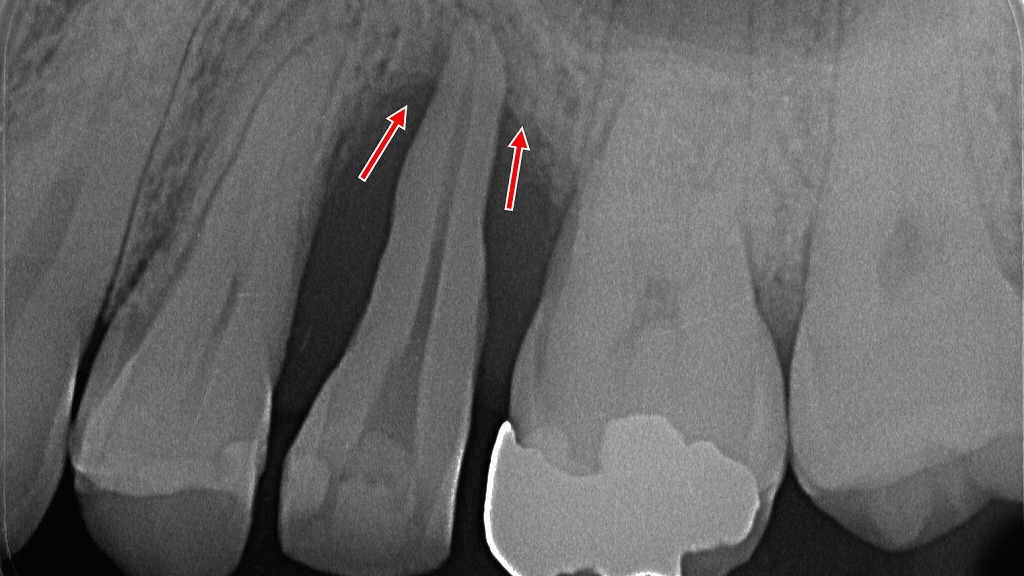

レントゲン画像で矢印が示す部分では、歯の周囲の骨(歯槽骨)が減少している様子が確認できます。

歯周病が進行すると、歯を支える骨が溶け、歯がグラグラと動揺するようになります。

放置すると、最終的には抜歯が必要になることもあるため、早期の歯周病治療が重要です。

赤矢印が示すように、歯根の先には大きな根尖病巣(膿の袋)が形成され、同時に歯周病による骨吸収が進行しています。歯を支える骨が大きく失われると、噛む力に耐えられず歯がグラグラします。このように「歯周病」と「根の感染(根尖病巣)」が重なると、急速に動揺が進むことがあり、早期の診断と治療が重要です。

重度歯周病で歯槽骨が破壊されたエックス線写真。

矢印で示した所が全体的に黒くなっています。これは遠心根周辺の骨がほとんど溶けているからです。